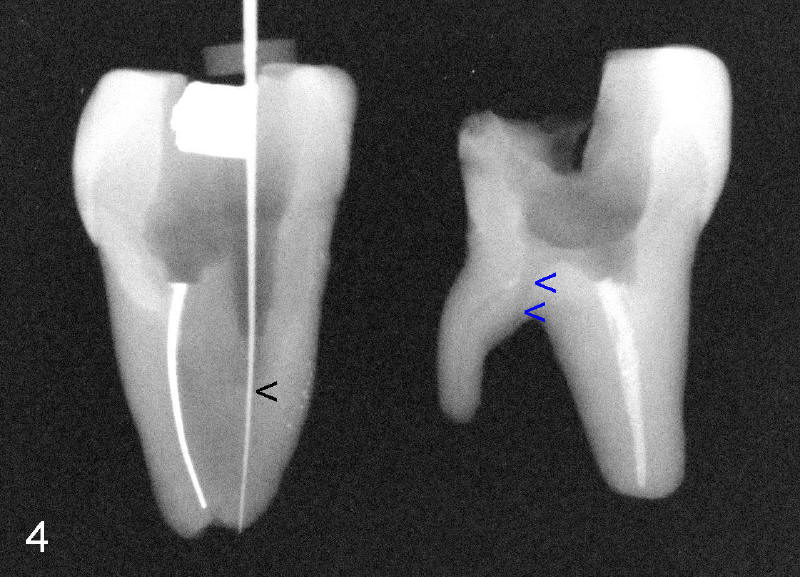

Fig.4: the distolingual canal is so obliterated that perforation is the end result (using rotary file) (blue arrowheads), back to main text